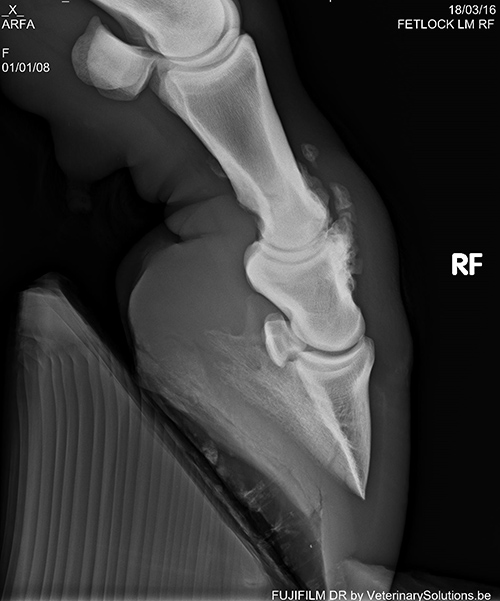

冠關節(jié)部位的 X 線片 - 關節(jié)炎